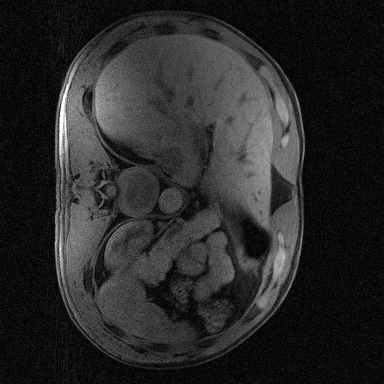

Supervised Deep-Learning (DL)-based reconstruction algorithms have shown state-of-the-art results for highly-undersampled dynamic Magnetic Resonance Imaging (MRI) reconstruction. However, the requirement of excessive high-quality ground-truth data hinders their applications due to the generalization problem. Recently, Implicit Neural Representation (INR) has appeared as a powerful DL-based tool for solving the inverse problem by characterizing the attributes of a signal as a continuous function of corresponding coordinates in an unsupervised manner. In this work, we proposed an INR-based method to improve dynamic MRI reconstruction from highly undersampled k-space data, which only takes spatiotemporal coordinates as inputs. Specifically, the proposed INR represents the dynamic MRI images as an implicit function and encodes them into neural networks. The weights of the network are learned from sparsely-acquired (k, t)-space data itself only, without external training datasets or prior images. Benefiting from the strong implicit continuity regularization of INR together with explicit regularization for low-rankness and sparsity, our proposed method outperforms the compared scan-specific methods at various acceleration factors. E.g., experiments on retrospective cardiac cine datasets show an improvement of 5.5 ~ 7.1 dB in PSNR for extremely high accelerations (up to 41.6-fold). The high-quality and inner continuity of the images provided by INR has great potential to further improve the spatiotemporal resolution of dynamic MRI, without the need of any training data.

翻译:在这项工作中,我们建议了一种基于IRI的方法,用这种方法来改进动态磁共振感应成像(MRI)重建,而该方法只是以高度低劣的 k-空间数据为基础,而该数据仅以磁共振坐标作为投入。具体地说,拟议的IRI将动态MRI图像作为一种隐含功能来表示,并将其编码到神经网络中。网络的权重仅从稀有的(k, t)空间数据本身中学习,而没有外部培训数据集或先前的图像。 利用基于IRI的强有力隐含性稳定化,同时不以清晰的动态和时空坐标坐标坐标坐标坐标作为投入。 拟议的IRIR将动态MRI图像作为一种隐含功能,将其编码到神经网络中。网络的权重仅从淡化的(k, t)空间数据本身学习,而没有外部培训数据集或先前的图像。